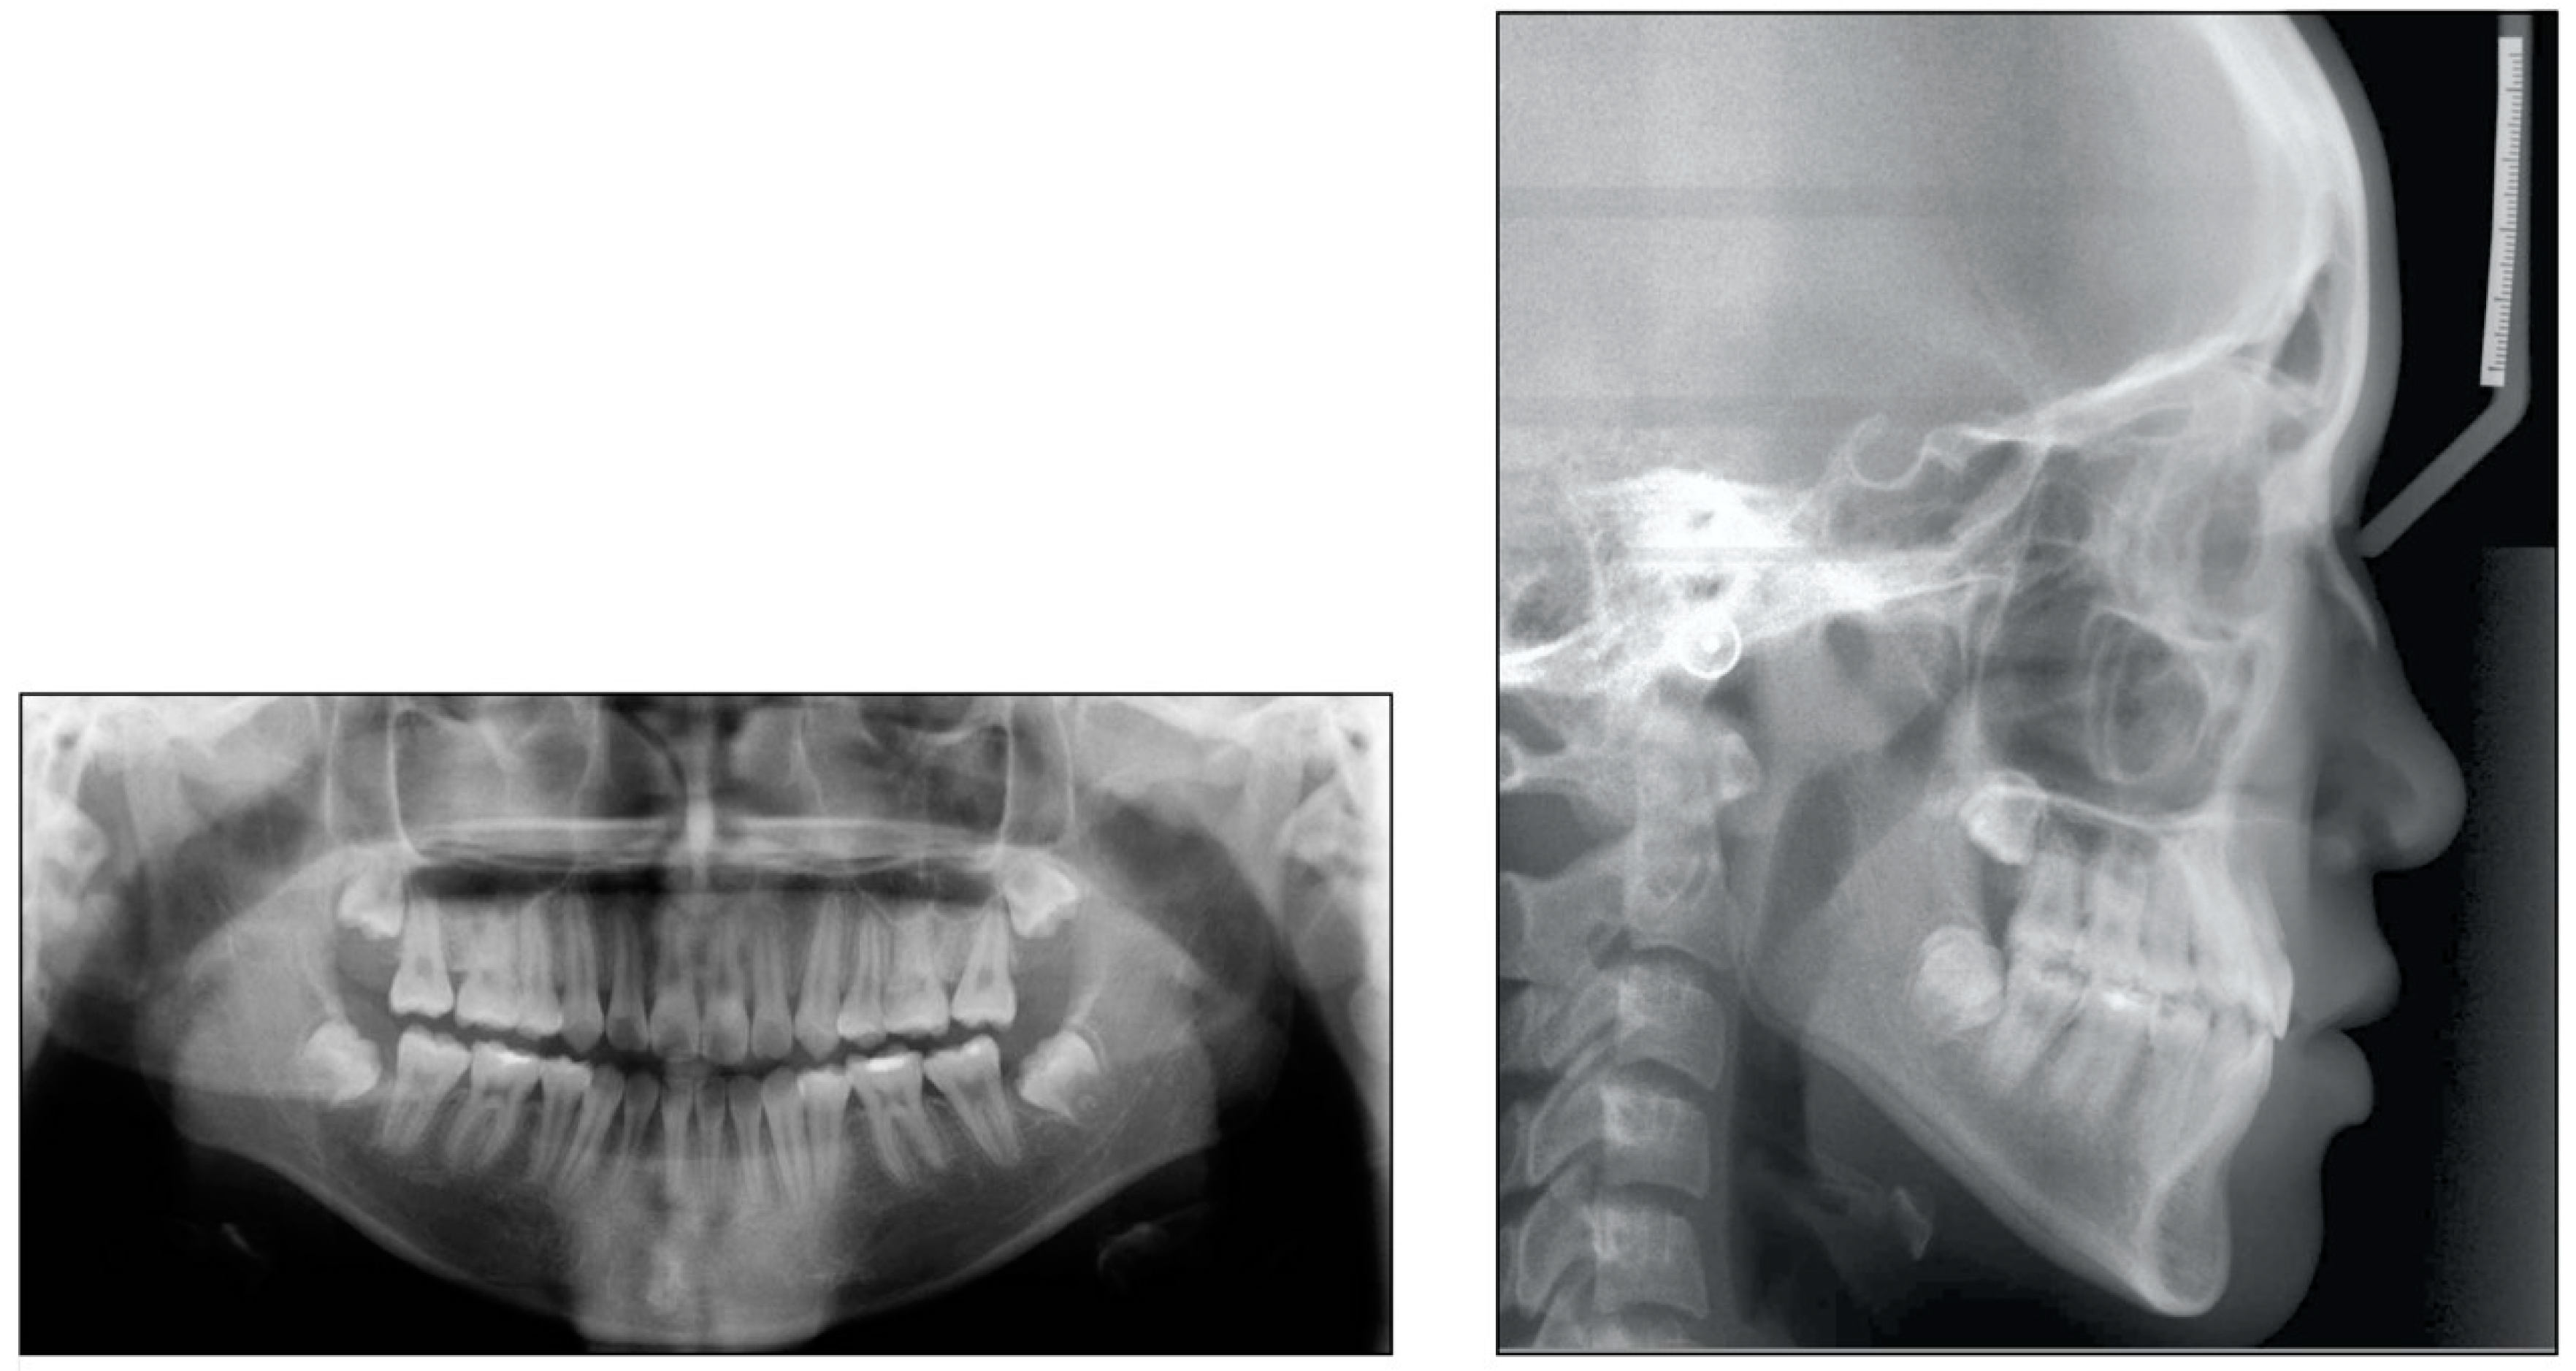

2.5. Treatment Results

3. Case 2

3.1. Diagnosis and Etiology